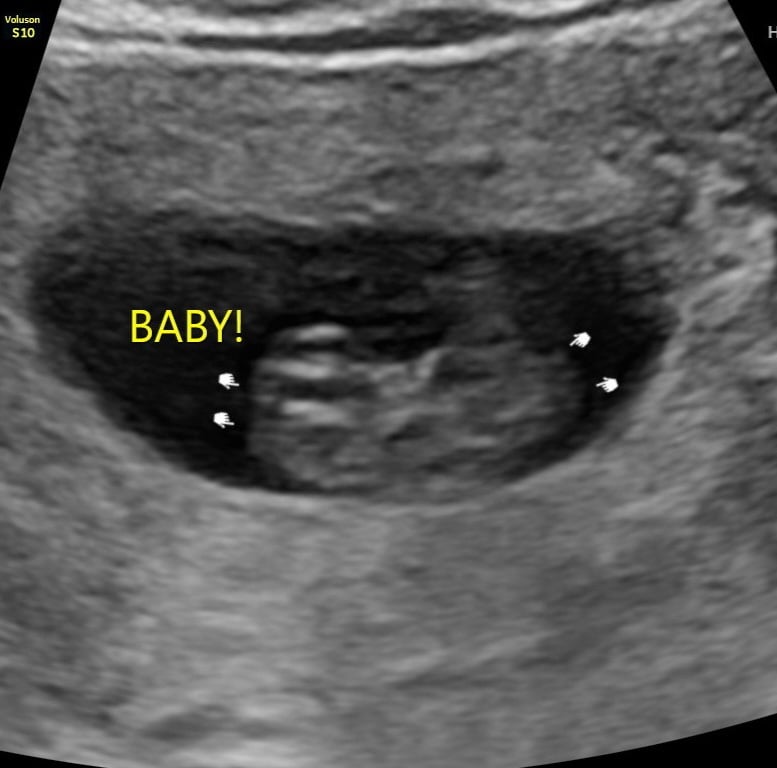

We had an early viability ultrasound due to previous complications. Not much to see at 5 weeks 2 days but everything that they should be able to see is there! Gestational sac and tiny little yolk sac. ❤️